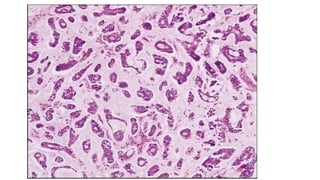

Section studied from R nasal mass shows tumor composed of tumor

cells arranged predominantly in cribriform and tubular pattern

tumor cells are small, round to oval with scanty cytoplasm,

hyperchromatic nuclei and indistinct cell border

pseudocyst formed by the tumor cells are filled with eosinophilic

hyaline material.

tumor cells are seen infiltrating the adjacent mucosal glands and

interstitium.

Neural invasion is seen

adjacent attached respiratory epithelium show normal histology

• Microscopic examination: Sectionstudied from R nasal mass shows tumor composed of tumor cells arranged predominantly in cribriform and tubular pattern tumor cells are small, round to oval with scanty cytoplasm, hyperchromatic nuclei and indistinct cell border pseudocyst formed by the tumor cells are filled with eosinophilic hyaline material. tumor cells are seen infiltrating the adjacent mucosal glands and interstitium. Neural invasion is seen adjacent attached respiratory epithelium show normal histology